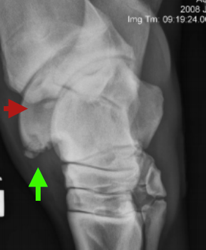

Osteochondritis Dissecans (OCD)